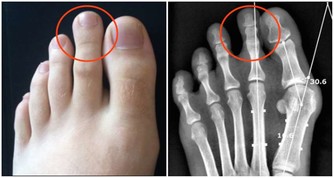

高尿酸除了傷害關節外,也會連累心血管系統和腎臟,因此應積極控制尿酸,其含量不能超過360微摩爾。少吃或不吃高嘌呤食物,多喝白開水,堅持運動來降低尿酸濃度;同時應定期做腎臟B超、腎功能檢查,用於評估腎臟是否健康。